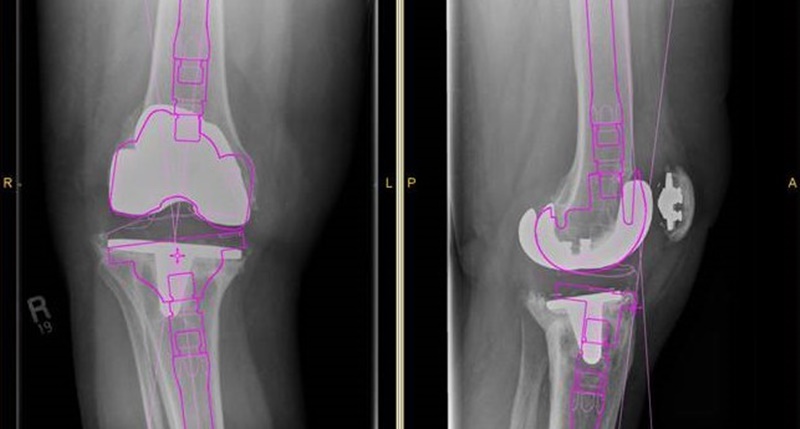

Case Study ประหยัดเวลาในการผ่าตัดหัวเข่าด้วยการวินิจฉัยตำแหน่งที่ถูกต้อง

การเตรียมการและวางแผนก่อนการผ่าตัด ช่วยให้ศัลยแพทย์ได้เข้าใจถึงลักษณะ ขนาดของอวัยวะผู้ป่วยที่กำลังเข้ารับการผ่าตัด เพื่อช่วยในการเลือกวิธีการผ่าตัดและเครื่องมือที่เหมาะสมกับคนไข้ ซึ่งส่งผลต่อการประหยัดเวลาที่มีค่าในห้องผ่าตัดได้

คนไข้หญิงชราวัย 80 ปีรายหนึ่ง เคยได้รับการผ่าตัดเปลี่ยนข้อเข่าเทียมเมื่อ 10 ปีที่แล้ว ซึ่งไม่นานมานี้เธอเริ่มมีอาการเจ็บและขาโค้งงอผิดรูป ที่เกิดจากการทรุดตัวของกระดูก Tibia ทำให้กระดูกบริเวณหัวเข่าเกิดการเบียดกัน

ทางทีมแพทย์จึงใช้การวางแผนการผ่าตัดด้วยโปรแกรม เพื่อทำการคาดคะเนขนาดของอุปกรณ์ที่ใช้ฝังในข้อเข่าของคนไข้ รวมถึงการเตรียมการอุปกรณ์ผ่าตัดอื่นๆ ให้พร้อมที่สุดในขณะผ่าตัด

การผ่าตัดนี้ใช้เทคนิคการ ฉีดยาชา (Spinal Anesthetic) โดยทำให้เกิดอาการชาและขยับส่วนล่างของร่างกายไม่ได้ประมาณ 2 ชั่วโมงครึ่ง ซึ่งการวางแผนการผ่าตัดด้วยโปรแกรมนี้ทีมแพทย์สามารถผ่าตัดเปลี่ยนข้อเข่าของคนไข้รายนี้เสร็จภายในเวลาที่กำหนด